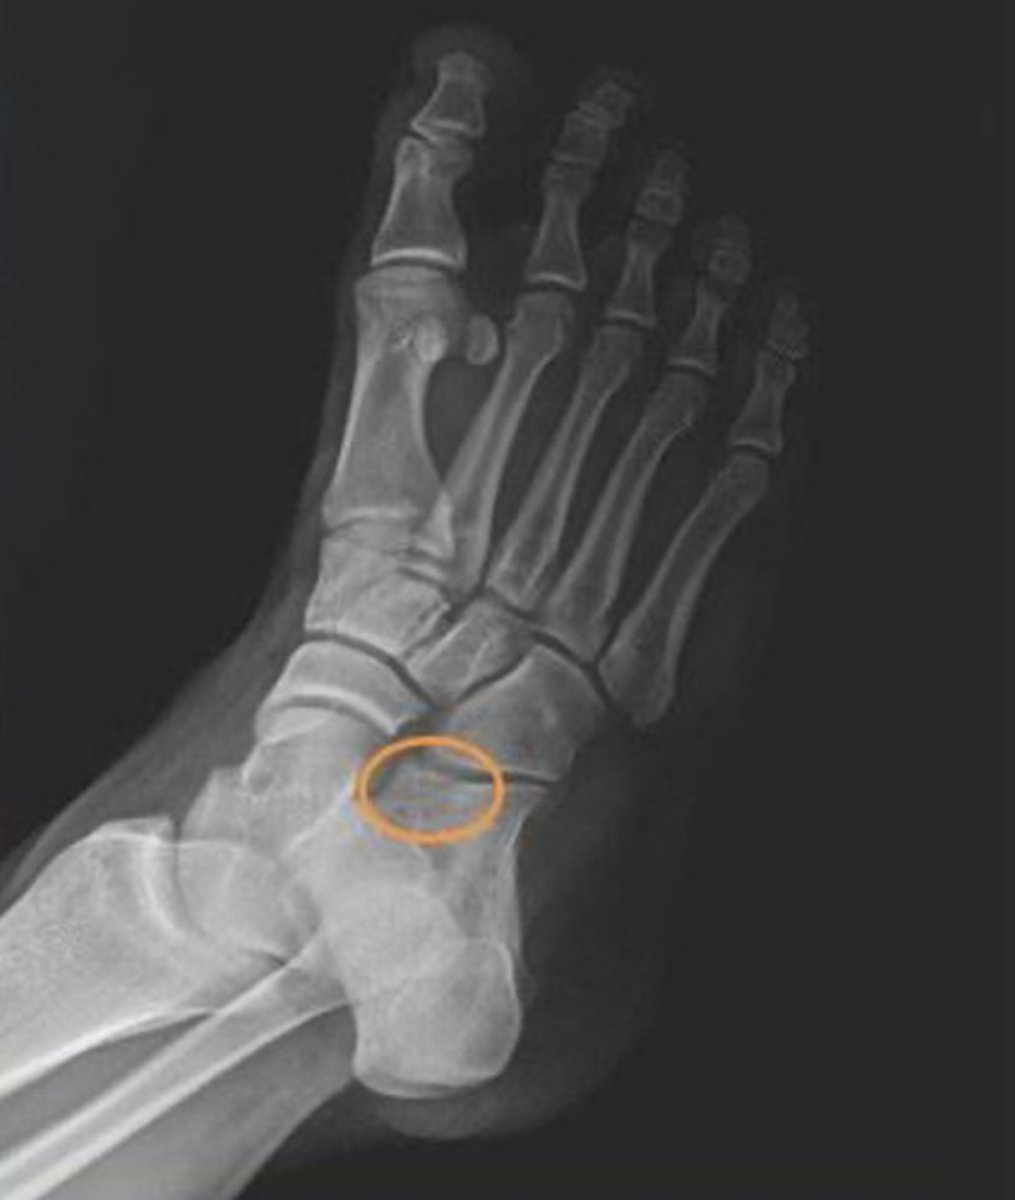

what radiograph view is this?

oblique

3 multiple choice options

what do the orange circles in these radiographs indicate about the patient's injury to the anterior process of the calcaneus?

avulsion fracture

2 multiple choice options